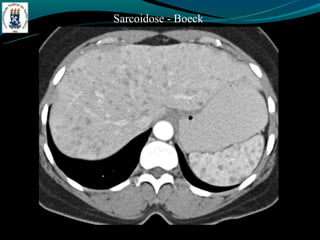

Sarcoidose - Boeck